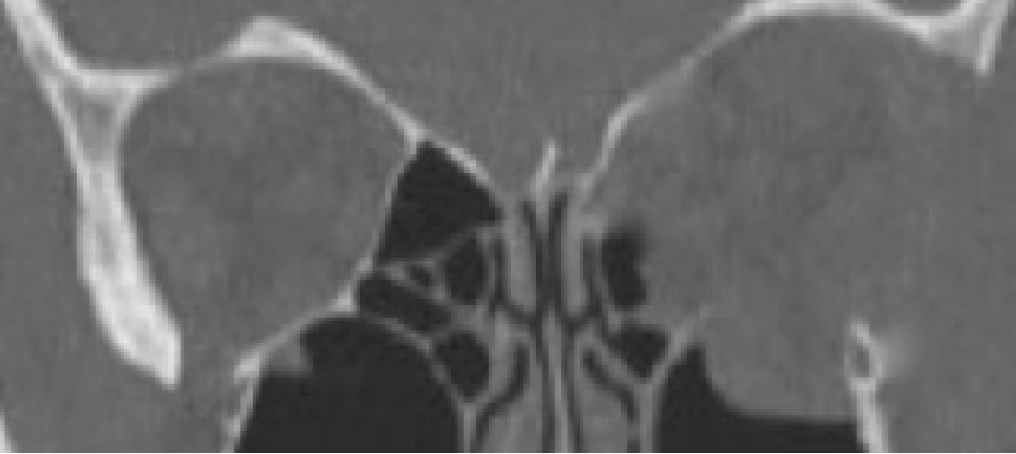

Figure 6. Coronal CT scan with classic pattern of extraocular muscle enlargement intensely involving the medial rectus muscles and less so the inferior rectus muscles.

Many times, medical therapy may reduce the disease burden in TED but not restore orbital and ocular function to the predisease state (Figures 5 and 6). As a result, rehabilitative surgery may be required. Unless the risk of permanent eye damage is suspected, orbital and periocular surgery should be avoided during the active phase to ensure the stability of surgical results. Surgical techniques and instrumentation have been greatly improved, now allowing surgery to be tailored for each patient. Preoperative orbital volumetric and orbital physiologic analysis may provide the adaptive surgeon the ability to better predict surgical outcomes. The introduction of intraoperative surgical navigation and instrumentation, such as piezoelectric bone removal systems, may afford safer, more strategic outcomes with orbital decompression (Figure 7). Algorithms developed for strabismus and eyelid surgery may improve ocular function and appearance.